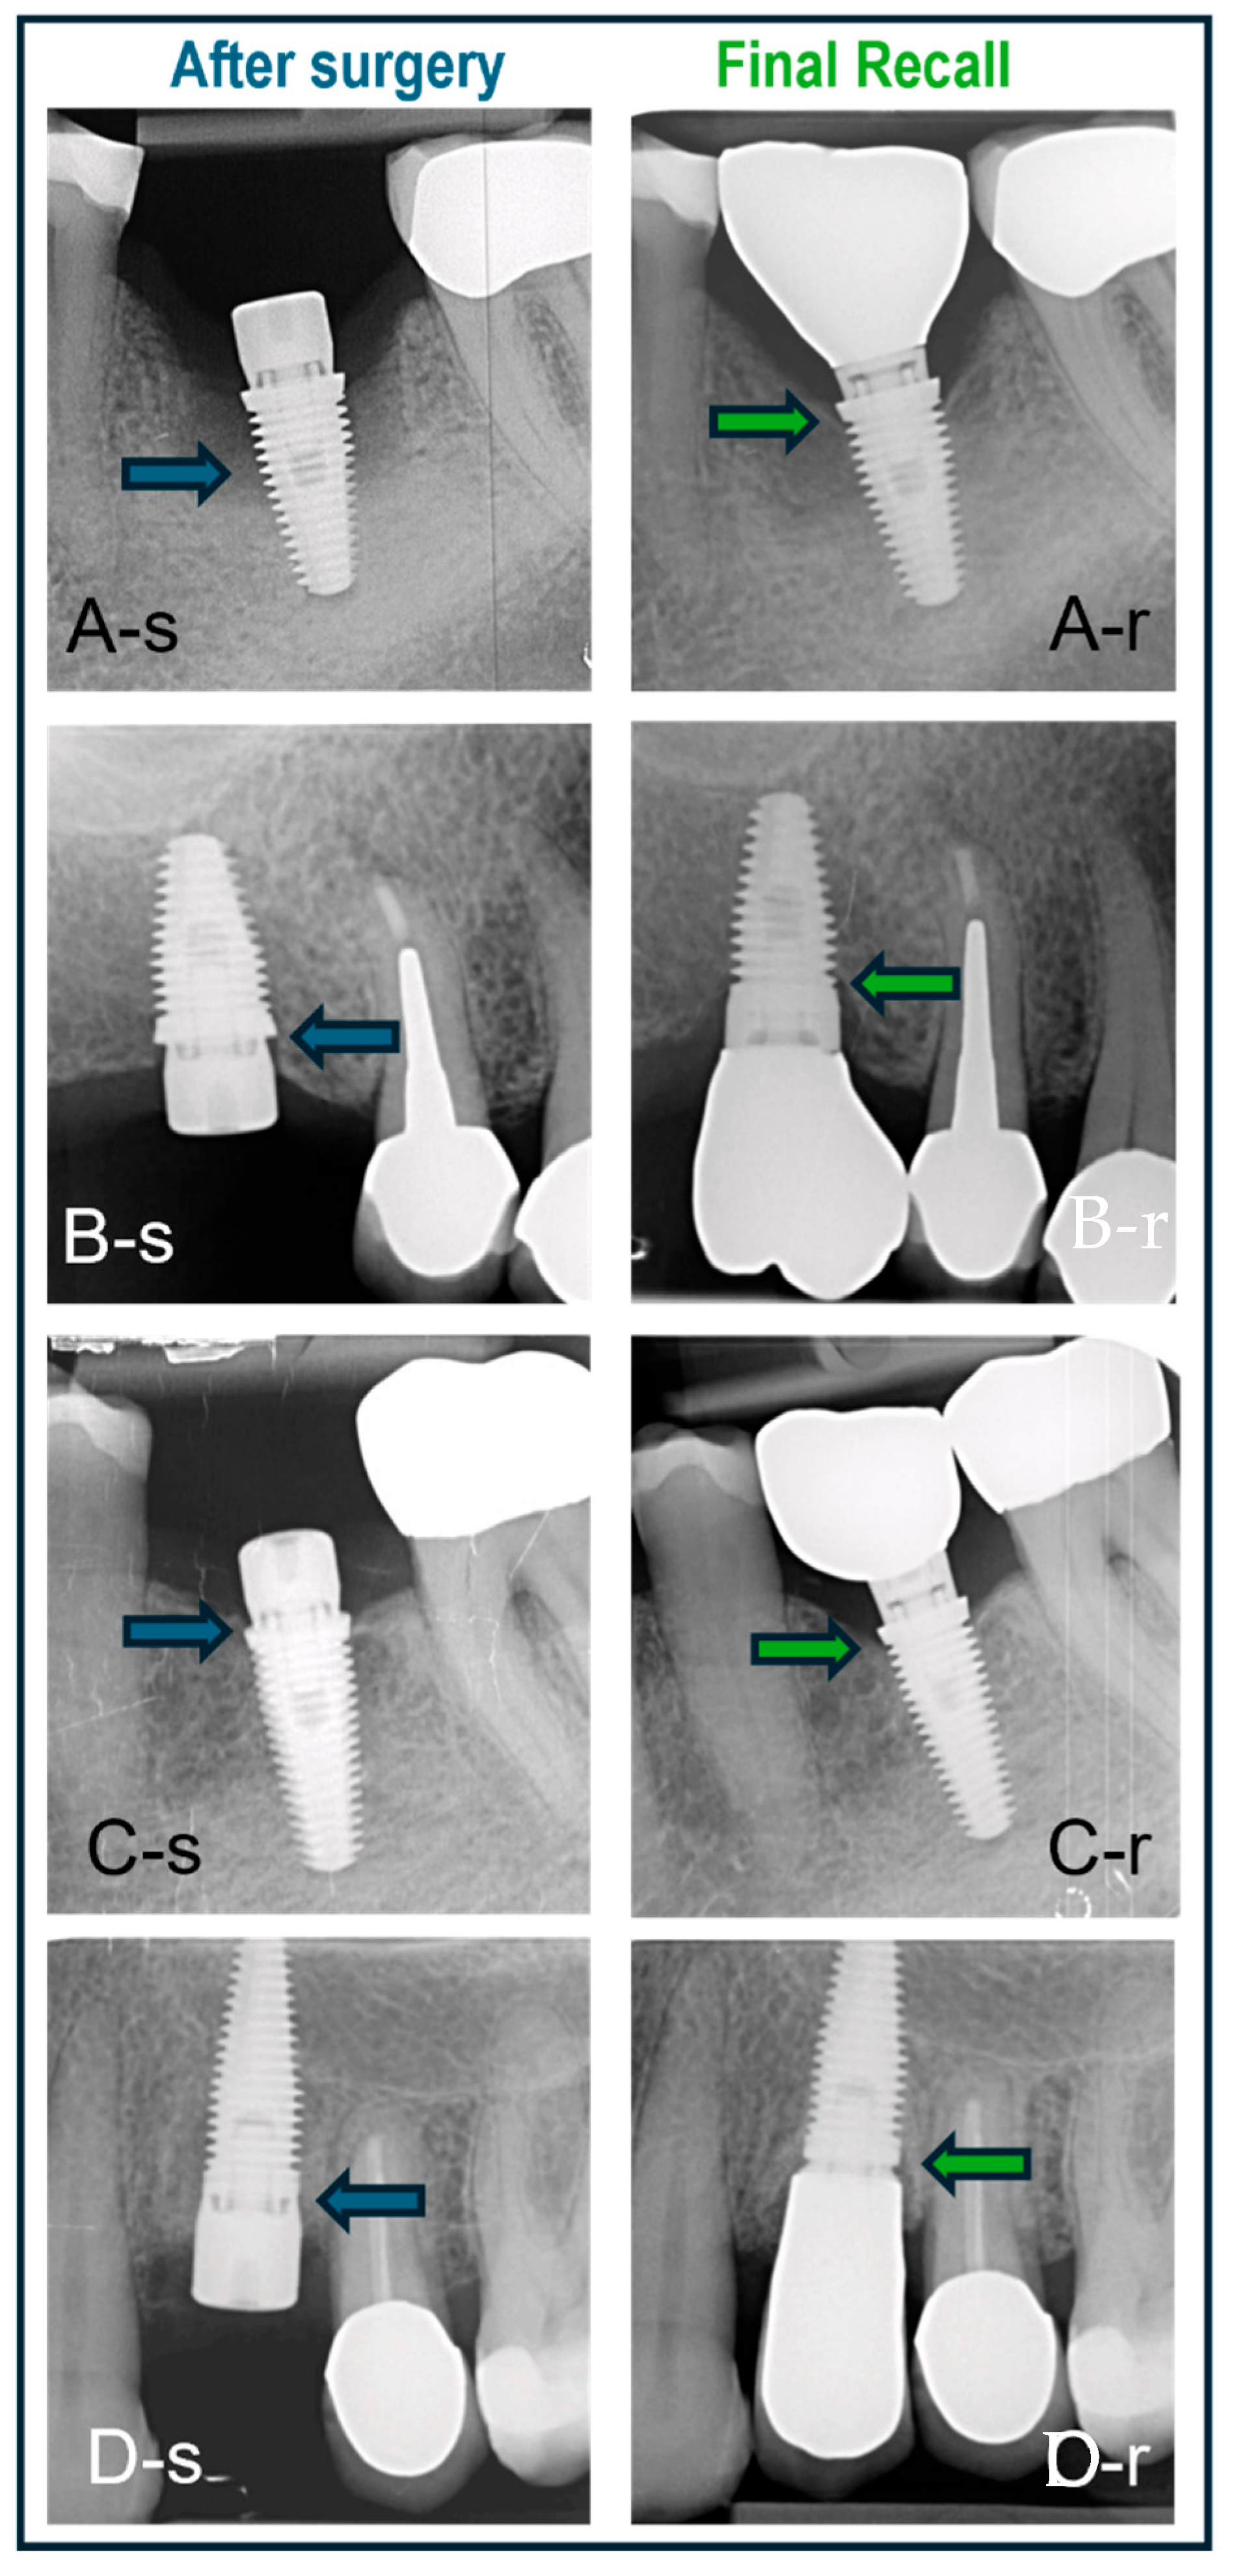

Some clinical cases representing the three surgical protocols with different implants are shown in Figure 7.

Figure 7.

Cases treated with various surgical protocols with baseline (-s) and final recall (-r) radiographs. The blue and green arrows indicate bone level at baseline and recall, respectively. (A) Immediate placement of a lower molar using a BAT implant placed in an intact socket without guided bone regeneration; bone regrowth and bone maturation in the socket are evident. (B) BAT implant placed flaplessly in healed bone followed by minimal bone remodeling; non-platform switched crown. (C) BAT implant with open flap followed by installation of platform-switched crown and minimal bone remodeling. (D) IBT implant placed in healed bone and restored with non-platform-switched crown and no signs of bone loss.

The implant cohort contained various types of implants, albeit with the same surface texture (Figure 7). Despite these variations in implant design, no statistically significant differences were observed in the bone level outcomes. Hence, the null hypothesis was not rejected. The existing literature comparing hybrid surface implants with moderately rough surface implants suggests that hybrid surfaces are a viable alternative, demonstrating comparable clinical, biomechanical, and radiographic performance [30]. Additionally, platform switching was applied to certain implants. According to previous research, platform switching can potentially reduce crestal bone loss by repositioning the implant–abutment junction toward the central axis of the implant, thereby minimizing the impact of mechanical and microbial factors on the crestal bone [31]. Platform switching was found to contribute to the preservation of crestal bone. It helps maintain bone level with minimal remodeling in thick soft tissues, while in thin tissues, it may not prevent bone loss [32]. Platform-switching implants, particularly when long abutments are used, show less marginal bone loss after 6 months and 1 year [33]. The practice-based study design allowed inclusion of a large sample treated in a daily clinic setting, which is often problematic in academic studies. Drawbacks and limitations of the study are related to the retrospective and non-randomized design, and hence, are missing a power calculation. The radiographs are not standardized, which may account for measurement errors when comparing different time points. Furthermore, only one surgeon was involved in the procedures, which may also induce a selection bias, and the peri-implant soft tissue condition was non-retrievable from the patients’ records. And last but not least, the study only focused on single implants. Although the MSc surface implants have shown a predictable short-term outcome, further prospective research with more controlled studies involving multiple teams and multiple indications is suggested. These should not only focus on long-term implant survival and bone stability but also include clinical peri-implant health parameters, as well as immunomarkers or bacterial profiling. The claims made by industry that the smooth surface affects bacterial adhesion in vivo and consequently results in a reduced peri-implantitis risk should be proven clinically for a wide range of indications, among others, at-risk patients.